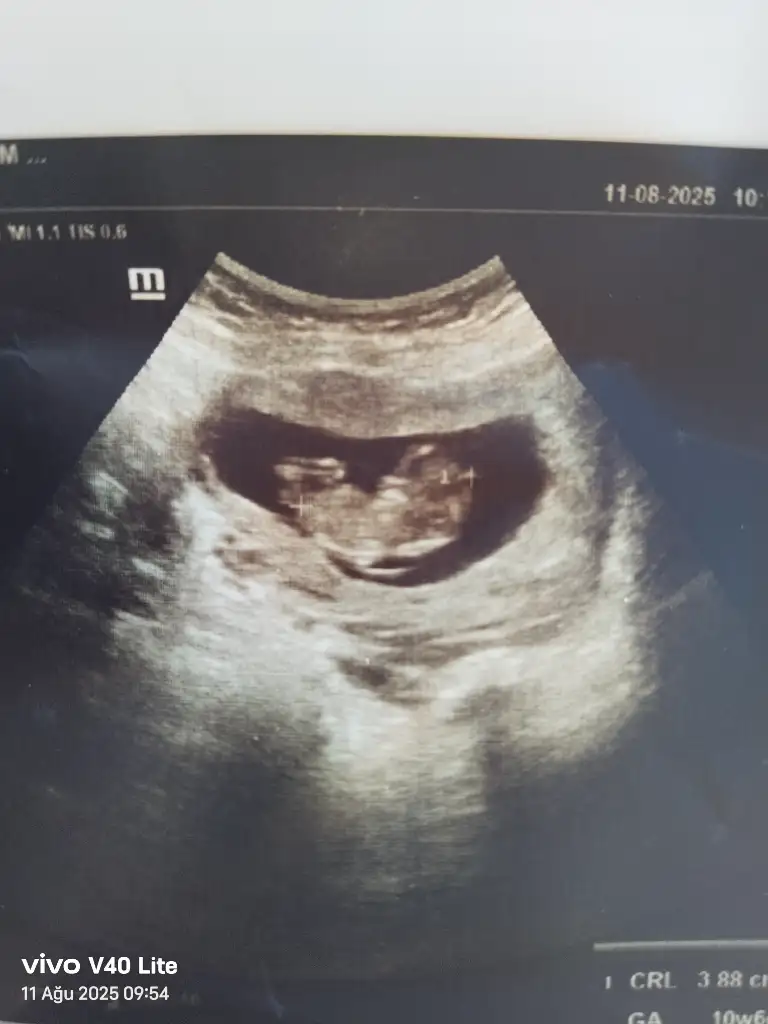

Merhaba benimde yorumlarmisiniz rica etsem 11+1Bariz erkek görüyorum, sağlıcakla gelsin inşallah![]()

Sizce benim nedir 11+1Erkek bence

Kesesini erkeğe benzettim sağlıkla gelsinSizce benim nedir 11+1

TeşekkürlerKesesini erkeğe benzettim sağlıkla gelsin![]()